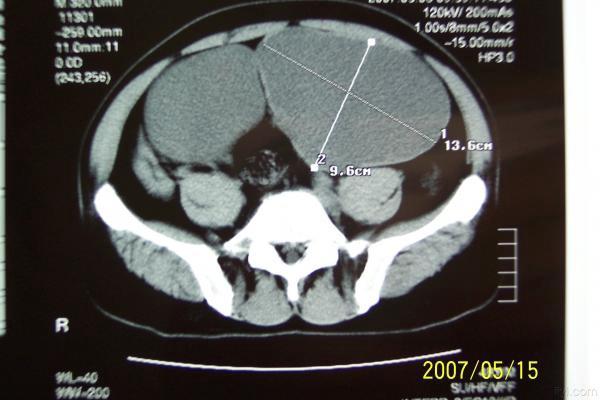

分享下一例巨大膀胱憩室的图片

分享下一例罕见病历的图片,这是我遇到的最大巨大膀胱憩室。